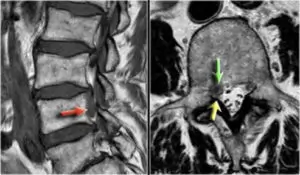

È importante consultare uno specialista in radiologia interventistica o un neurochirurgo per diagnosticare e trattare correttamente il dolore discogeno. La diagnosi può essere supportata tramite tecniche avanzate di imaging, come la risonanza magnetica (RM) o la tomografia computerizzata (TC), che permettono di osservare in dettaglio la condizione dei dischi e delle strutture circostanti.